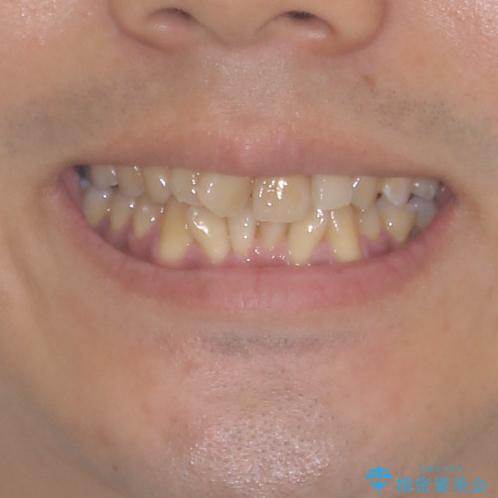

上顎の狭い歯列をインビザラインで拡大

- 上下前歯の叢生を気にして来院された患者様です。

奥歯はクロスバイトとなっているので上顎は側方拡大を行いつつ、上下全体の叢生をインビザラインにより改善することとしました。

治療途中でクリーニングやホワイトニングを行い、歯列が整うと同時に明るい口元となりました。